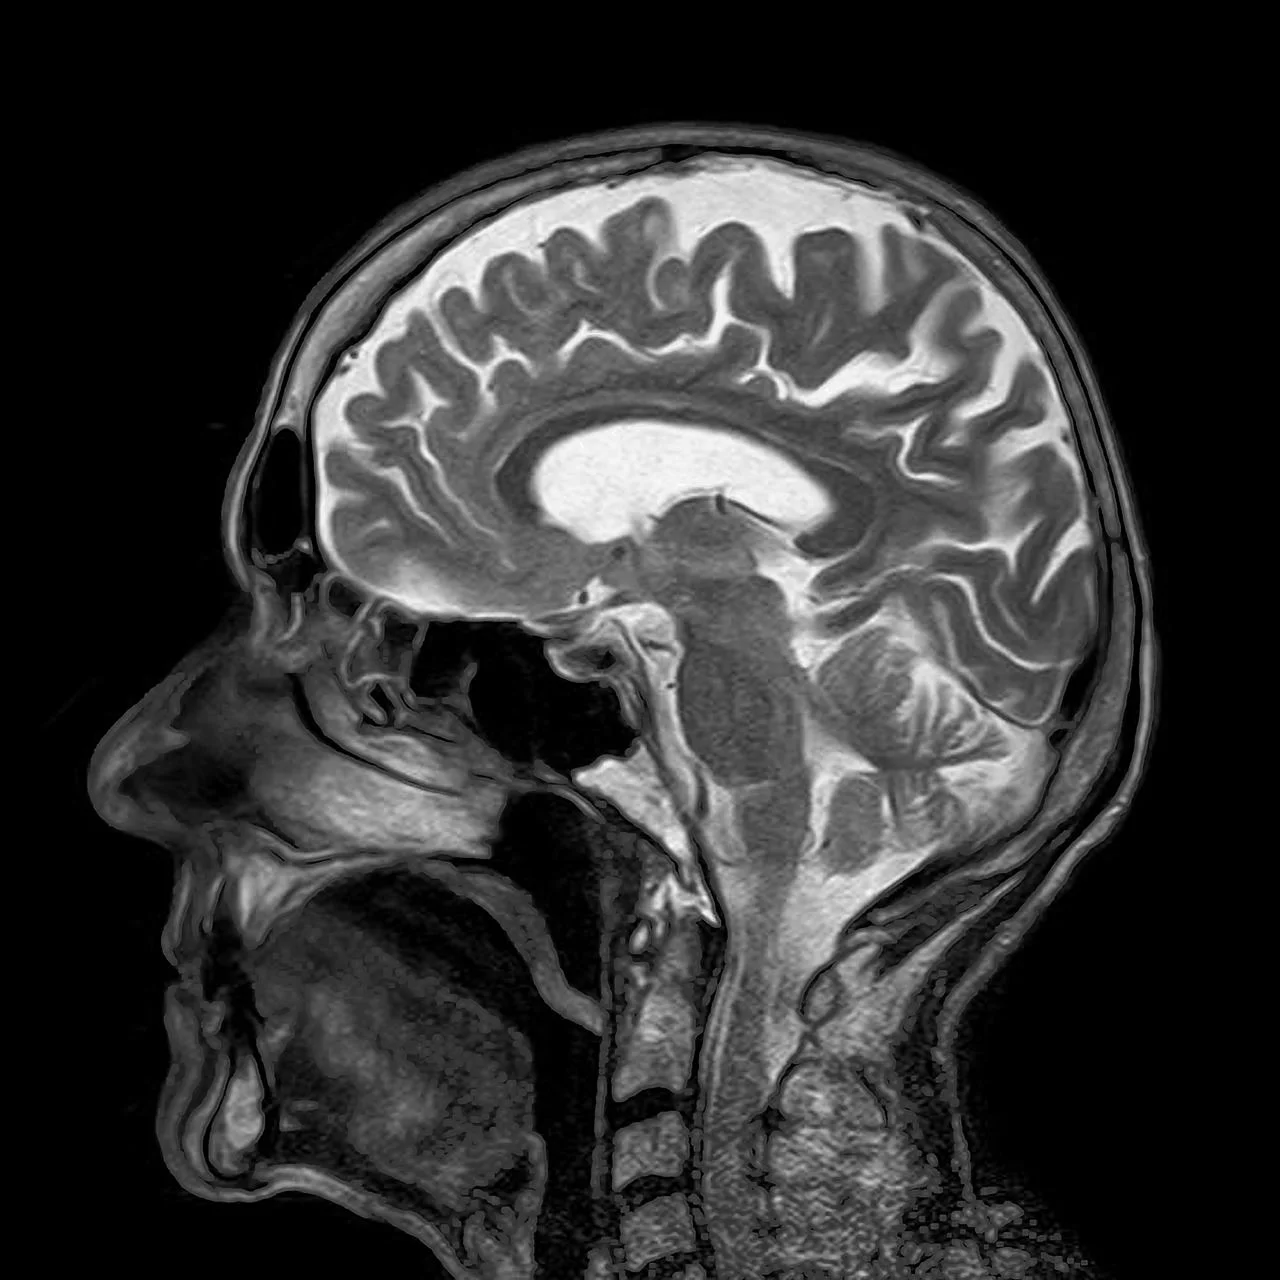

As shown in this picture, they simply contain a beta-lactam ring in their molecular structures. R